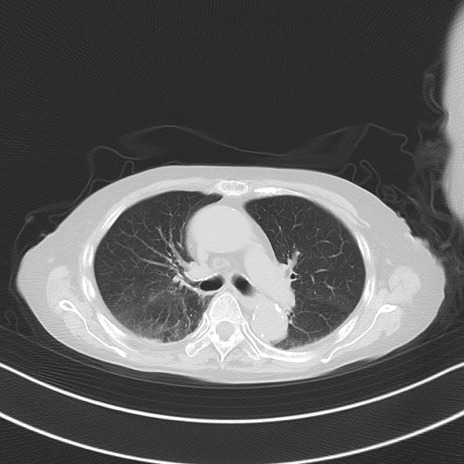

横断像

他院CT